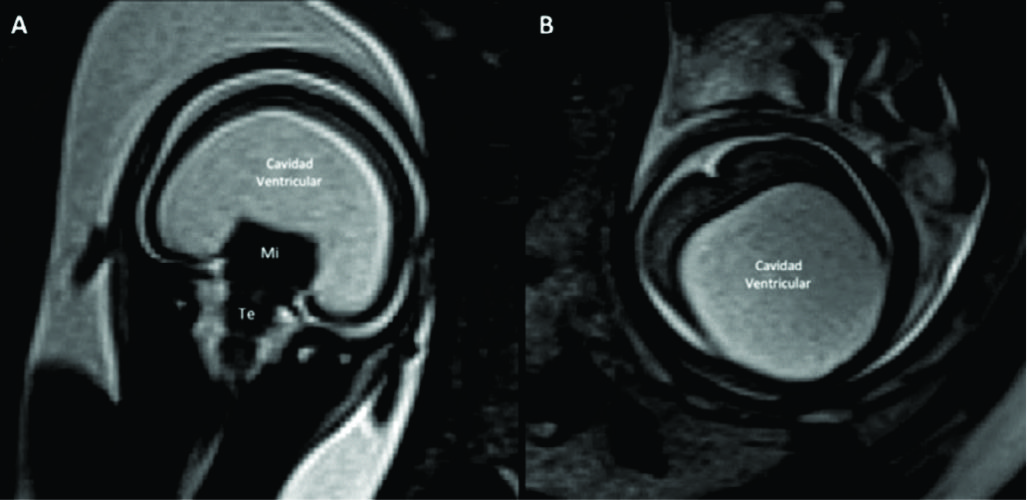

Figura 7

RM Fetal Holoprosencefalia.

RMf a las 28 semanas referido por estudio ecográfico para confirmación de holoprosencefalia. En el plano coronal (A) se identifica la cavidad ventricular única con manto cerebral periférico adelgazado y la característica masa intermedia (MI) por la ausencia de división de ambos tálamos.

En el plano axial (B) los hallazgos son similares con ausencia de estructuras de la línea media como cisura inter-hemisférica u hoz cerebral. Te: Tronco encefálico